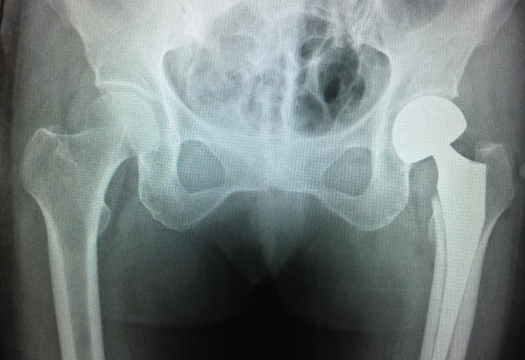

术前

检查显示,老人左股骨颈骨折,已经移位,手术指征明确。

术后

手术一共进行了50分钟,很顺利,很成功。术中,手术小组根据术前的测量截断股骨颈,取出股骨头,安装试模股骨柄及球头,仔细测试并调整关节稳定性及肢体长度,复位髋关节后再次测试稳定性,最后逐层封闭切口,留置引流管。